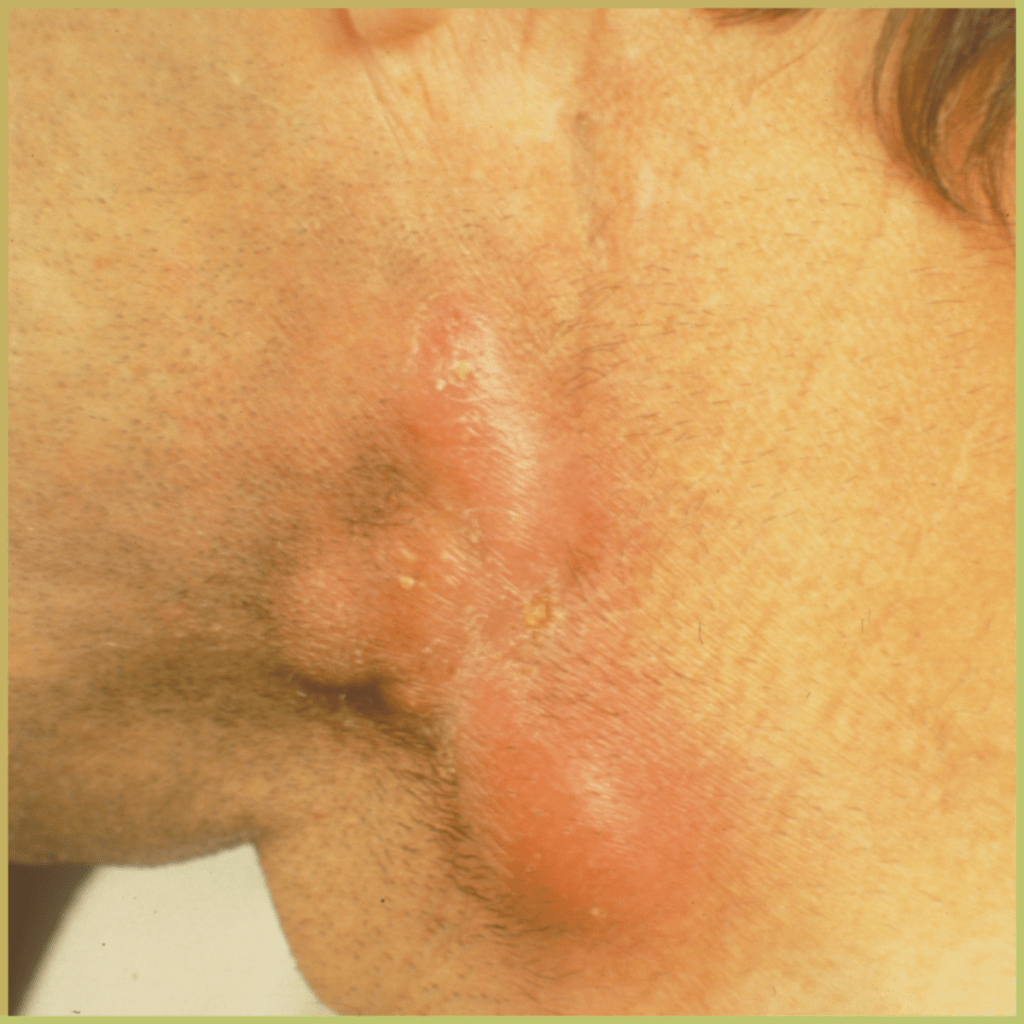

ACTINOMYCOSIS

Actinomycosis is a rare infection caused by filamentous anaerobic gram-positive bacteria of the Actinomycetaceae family, mainly the israelii species. The disease leads to suppurative and granulomatous soft tissue lesions. Risk factors for actinomycosis include immunosuppression, osteoradionecrosis, leukemia, and mucosal damage. The common clinical presentation includes:

- Pain, paresthesia, low-grade fever, and persistent swelling.

- Discharge with drainage fluid containing yellow sulfur granules (bacterial colonies).

- Hard, chronic enlargement of the jaw.

- Bone lesions may be destructive with accompanying rarefaction and/or sclerosis.

- Mandible is the most common site.

Diagnosis can be challenging because of nonspecific presenting signs (pain, edema) and nonspecific imaging findings (necrotic/cystic areas surrounded by fibrosis). Diagnosis is based on the lesion history, clinical presentation and cytological findings, which may include:

- Peripheral club-like structures in bacterial colonies.

- Positive bacterial culture.

Your differential diagnosis should include:

- Another infection (fungal, staphylococcal, streptococcal).

- Malignant neoplasm.

Treatment options include:

- Surgical debridement.

- Antibiotics (penicillin).